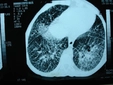

Temiz Akciğer Tomografisi Ne Anlama Geliyor?Günümüzde tıpta tanı ve tedavi süreçlerinde önemli bir yer tutan görüntüleme yöntemlerinden biri olan akciğer tomografisi, hastalıkların teşhisinde kritik bir rol oynamaktadır. "Temiz akciğer tomografisi" ifadesi, genellikle akciğerlerde herhangi bir anormal bulguya rastlanmadığı anlamına gelir. Bu bağlamda, temiz bir akciğer tomografisi sonucu, hastanın akciğer sağlığının iyi olduğunu gösterir. Akciğer Tomografisi Nedir?Akciğer tomografisi, yüksek çözünürlüklü görüntüler elde etmek için X-ray teknolojisini kullanan bir görüntüleme yöntemidir. Bu yöntem, akciğerlerin iç yapısının detaylı bir şekilde incelenmesine olanak tanır. Tomografi, akciğerlerdeki lezyonlar, tümörler, enfeksiyonlar ve diğer patolojilerin tespit edilmesinde son derece etkili bir yöntemdir. Temiz Akciğer Tomografisi SonucuTemiz bir akciğer tomografisi sonucu, şu durumları ifade edebilir: